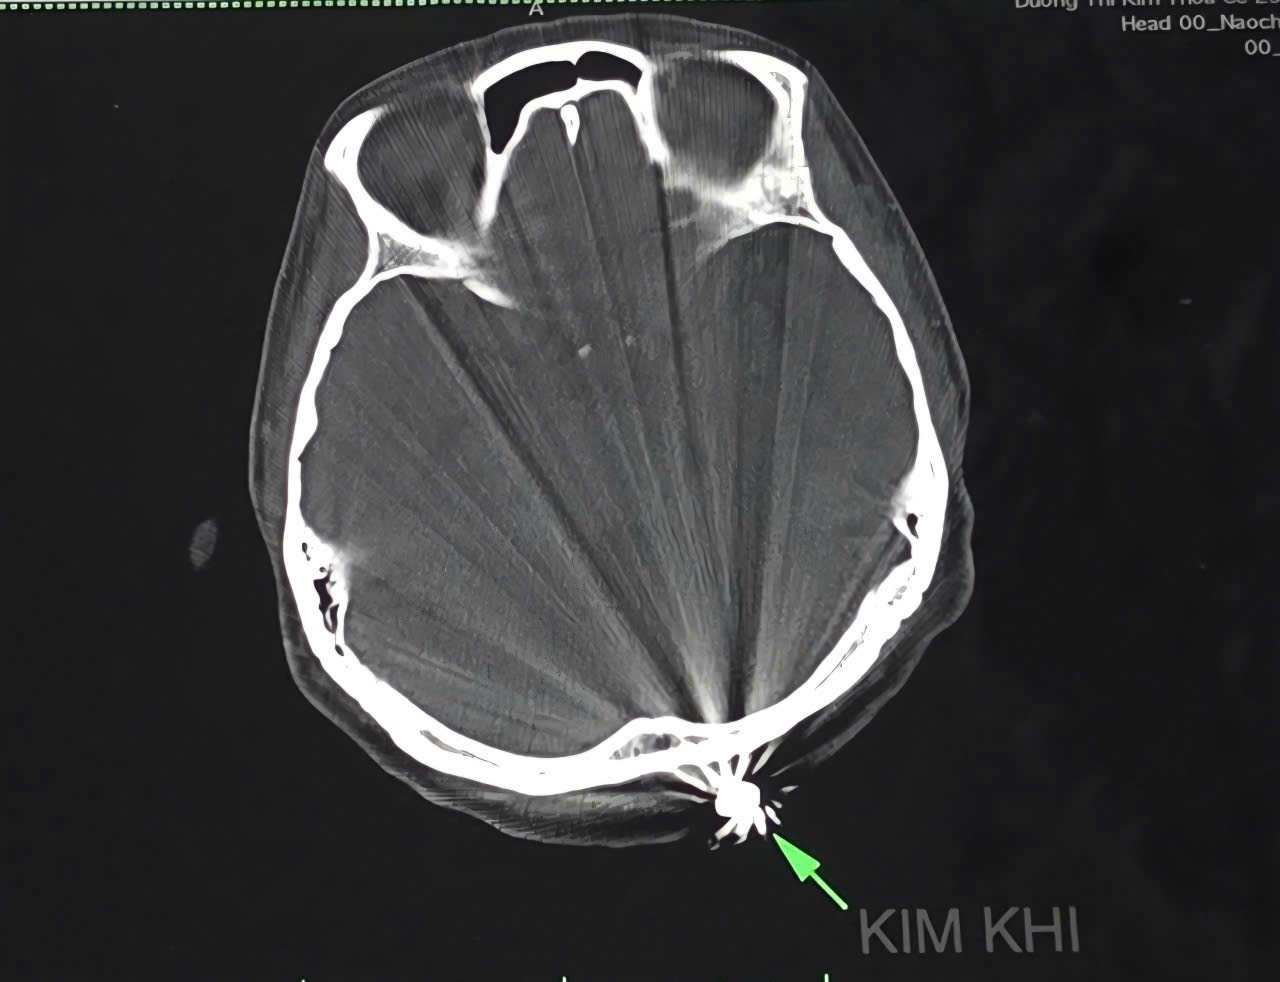

![]() |

Hình ảnh trên phim CTScan. |